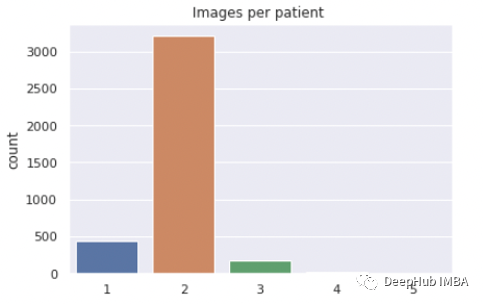

总共有3851名患者:

- 1张图像患者:446例

- 2张图像患者:3208例

- 3张图像患者:181例

- 4张图像患者15例

- 5张图像患者:1例.